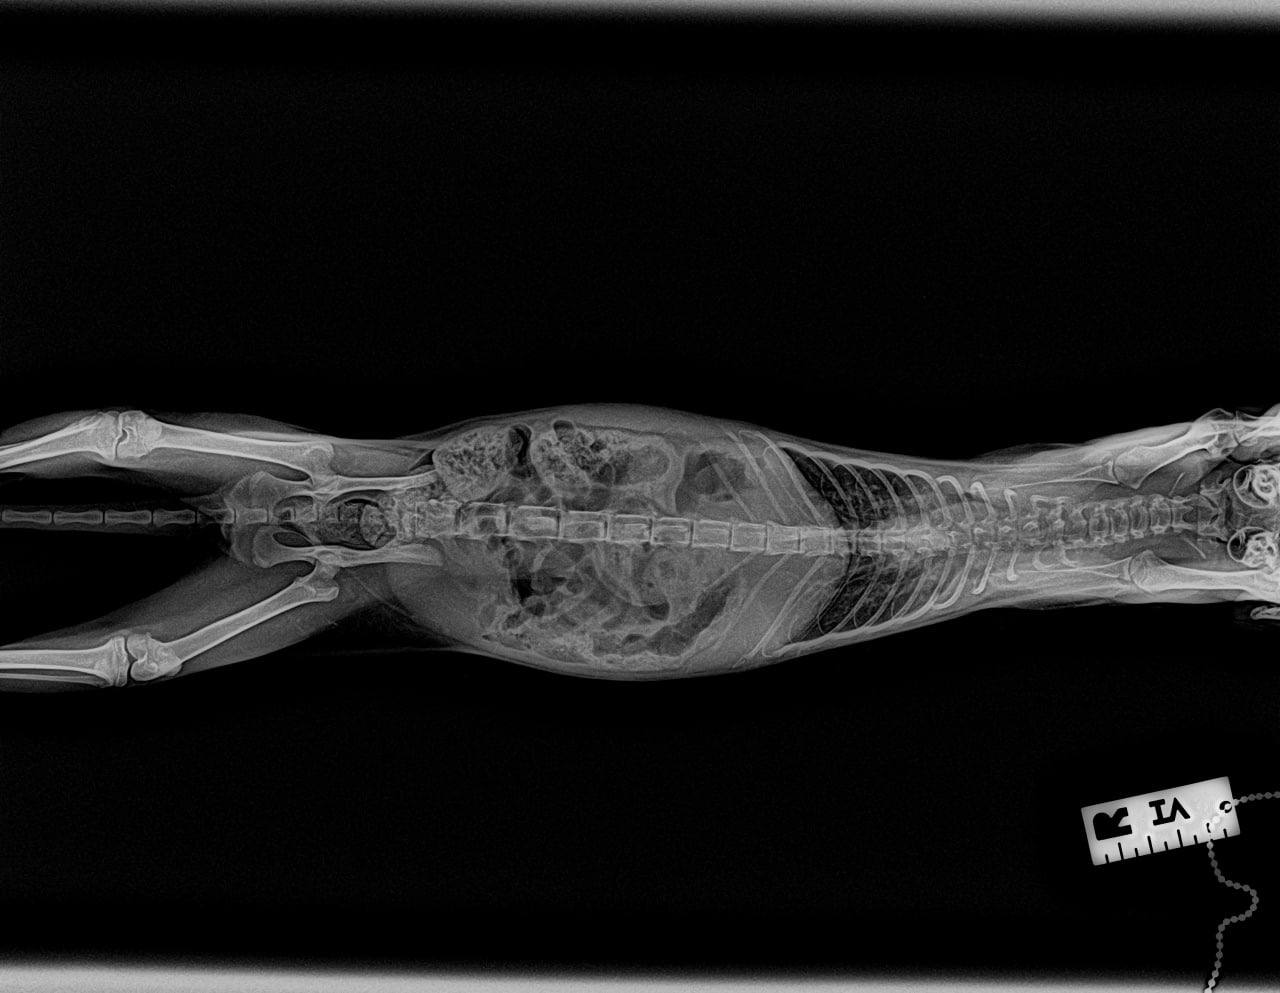

Багги еще сделали контрольный рентген в долг перед клиникой. Пока без видимых улучшений, скорректировали лечение, верим!

кашель продолжается, рентген пока не вдохновляет, есть подозрения на астму... 😔 Вкололи кортизон и наблюдают…